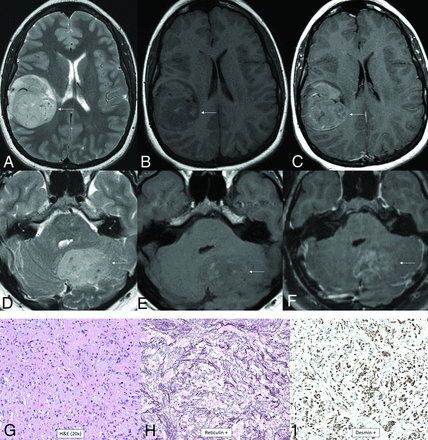

Diffuse hemispheric glioma, H3 G34-mutant. Multifocal masses are seen in the right temporal and parietal lobes. The temporal mass shows heterogeneously increased T2 signal (A), heterogeneously low T1 signal with a few foci of T1-hyperintense hemorrhage (B), and heterogenous enhancement (C, arrows). The parietal mass shows similar signal characteristics with heterogeneous T2-FLAIR hyperintensity (D), T1-hypointensity (E), and enhancement (F, arrows). The histologic section reveals an infiltrating glioma with astrocytic morphology (G). Glioma cells are positive for ATRX (H) and GFAP (I) stains and negative for IDH1 R132H and OLIG2. There was a high Ki-67 proliferation index of up to approximately 20%. This immunophenotype suggested a mutation of H3 G34, warranting further genomic evaluation. Next-generation sequencing revealed a somatic mutation in H3-3A (also known as H3F3A). Currently, there are no clinically approved therapies specifically targeting H3-3A mutations.

Diffuse Pediatric-Type High-Grade Glioma, H3 Wild-Type and IDH Wild-Type